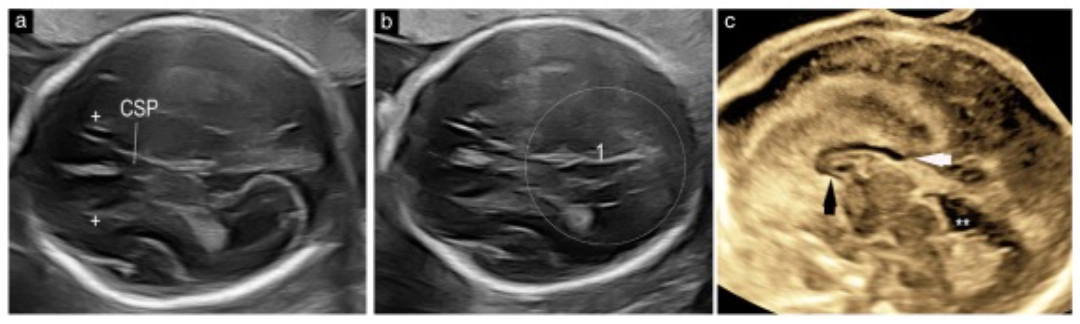

Feto con pACC a las 27 semanas. Se observa cavum septi pellucidi anormal (índice < 1.5), alteraciones en el complejo posterior y ausencia de segmentos del cuerpo calloso en el plano sagital. Fuente: Viñals et al., 2025.